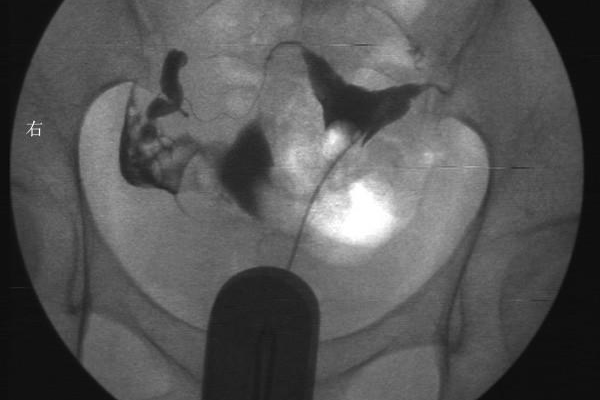

輸卵管造影對子宮會有一定傷害,但傷害幾乎可以忽略不計。因為輸卵管造影是侵入性檢查,不像超聲一樣方便。需要把造影管放入患者的子宮腔內,然後再打造影劑,接著在超聲下或X線下監測造影劑的彌散情況。在操作過程中,容易誘發逆行感染,同時造影劑進入子宮腔內對子宮內膜也會有一定損傷。